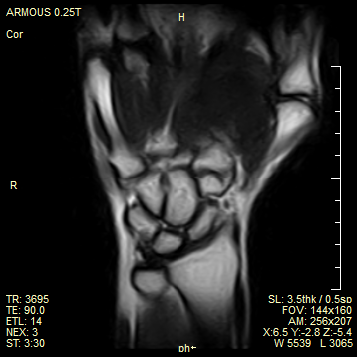

媲美高场 高效诊疗

成像效果媲美高场强设备,完全满足骨科诊断需求